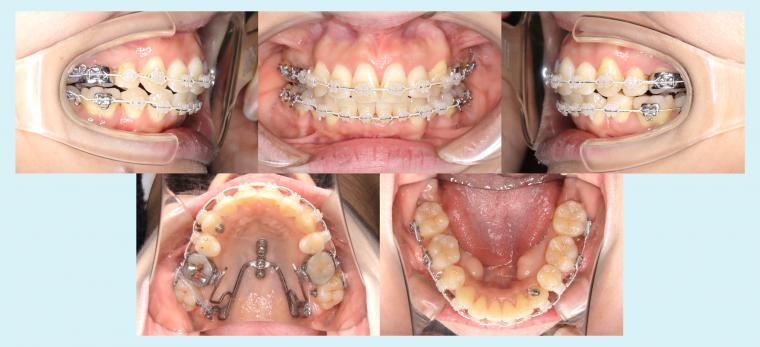

#47 アイステーションを使用した非対称症例